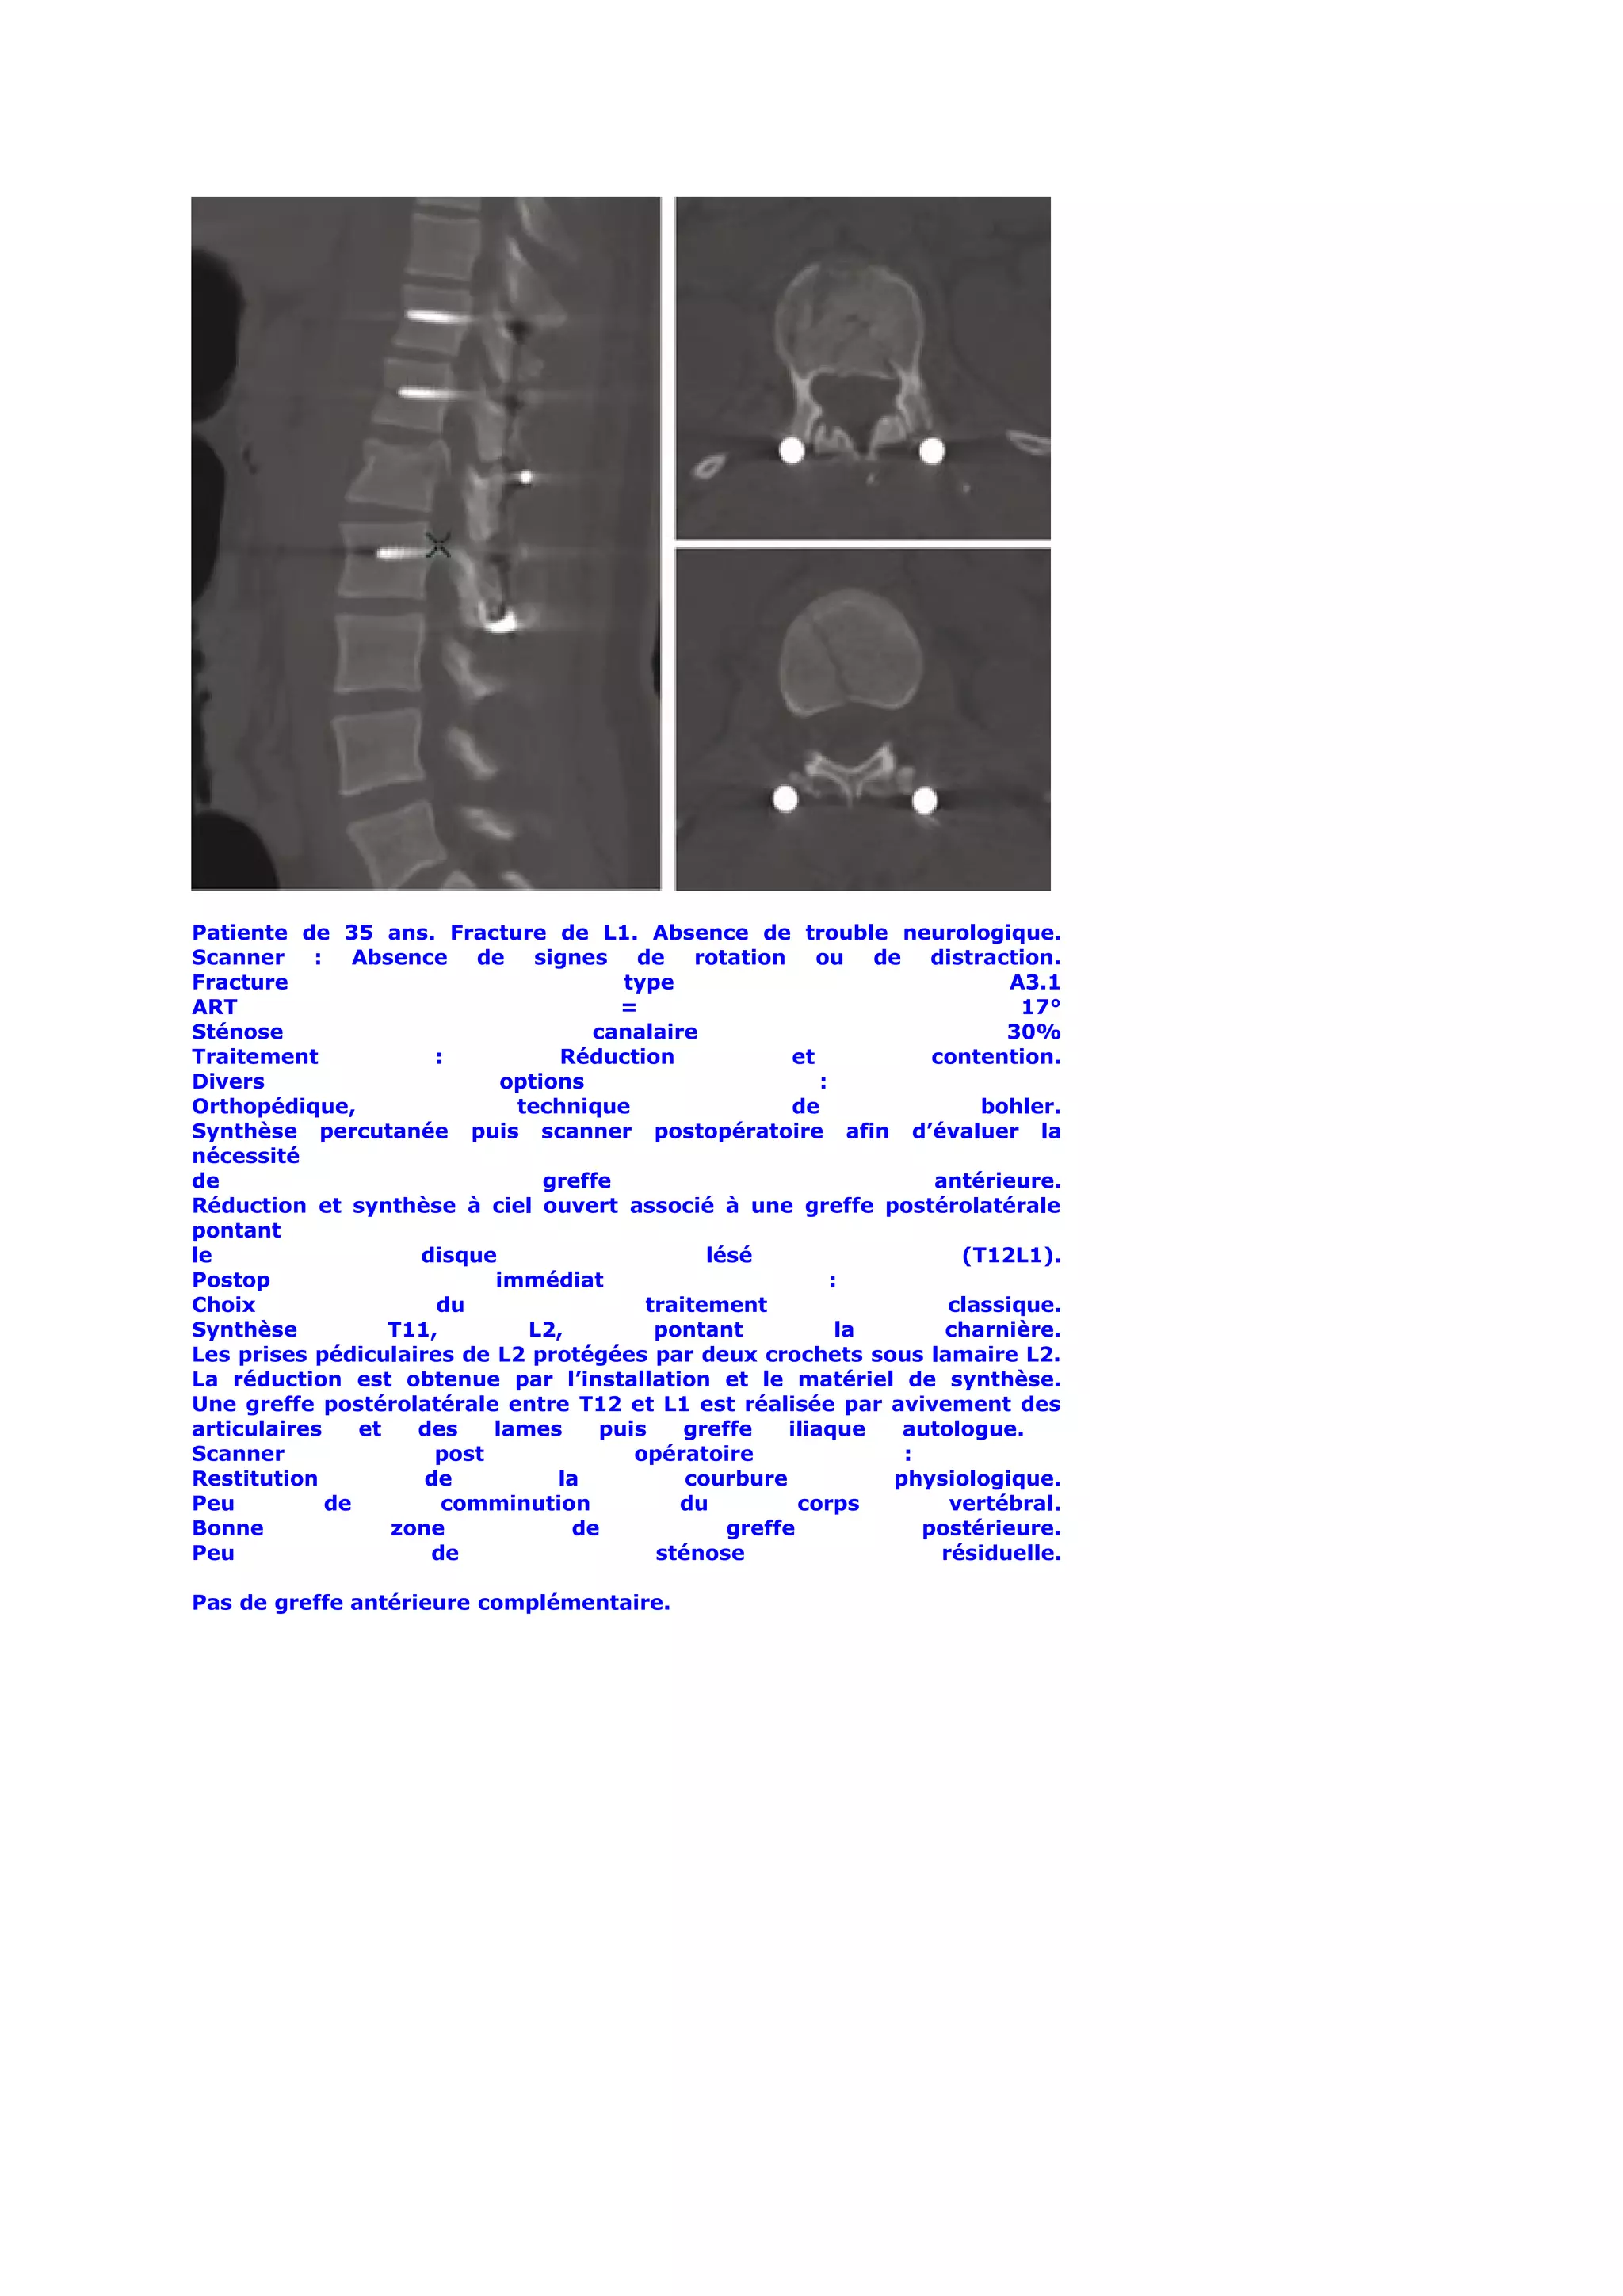

Patiente de 35 ans. Fracture de L1. Absence de trouble neurologique.

Scanner : Absence de signes de rotation ou de distraction.

Fracture                                type                                  A3.1

ART                                     =                                      17°

Sténose                              canalaire                               30%

Traitement             :          Réduction             et            contention.

Divers                       options                        :

Orthopédique,                 technique                 de                 bohler.

Synthèse percutanée puis scanner postopératoire afin d’évaluer la

nécessité

de                               greffe                               antérieure.

Réduction et synthèse à ciel ouvert associé à une greffe postérolatérale

pontant

le                   disque                     lésé                     (T12L1).

Postop                      immédiat                          :

Choix                  du                 traitement                    classique.

Synthèse           T11,        L2,         pontant             la      charnière.

Les prises pédiculaires de L2 protégées par deux crochets sous lamaire L2.

La réduction est obtenue par l’installation et le matériel de synthèse.

Une greffe postérolatérale entre T12 et L1 est réalisée par avivement des

articulaires    et   des    lames     puis    greffe    iliaque    autologue.

Scanner                post              opératoire                :

Restitution           de          la          courbure            physiologique.

Peu          de         comminution          du          corps          vertébral.

Bonne              zone            de             greffe             postérieure.

Peu                   de                   sténose                     résiduelle.

Pas de greffe antérieure complémentaire.